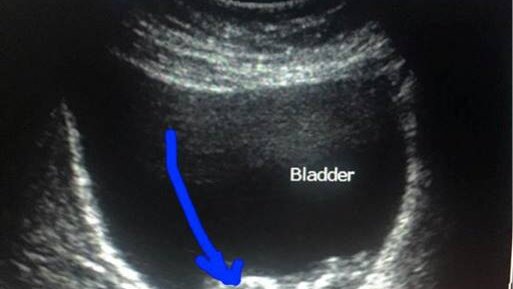

В открытом доступе разместили интереснейший случай из Северодонецка. Пациентке 38 лет, двое родов - два кесаревых сечения в нижнем маточном сегменте. Третья (или четвертая? - не суть) беременность. В 7 недель выполнялось УЗИ – все было в полном порядке.

В сроке 11-12 недель появились боли при мочеиспускании, кровь в моче, острая задержка мочи, цисталгия, восходящий пиелонефрит.

При УЗИ обнаружен неразвивающийся плод, самостоятельно "мигрировавший" в материнский мочевой пузырь, хорион в полости матки, функционирующая пузырно-маточная фистула...